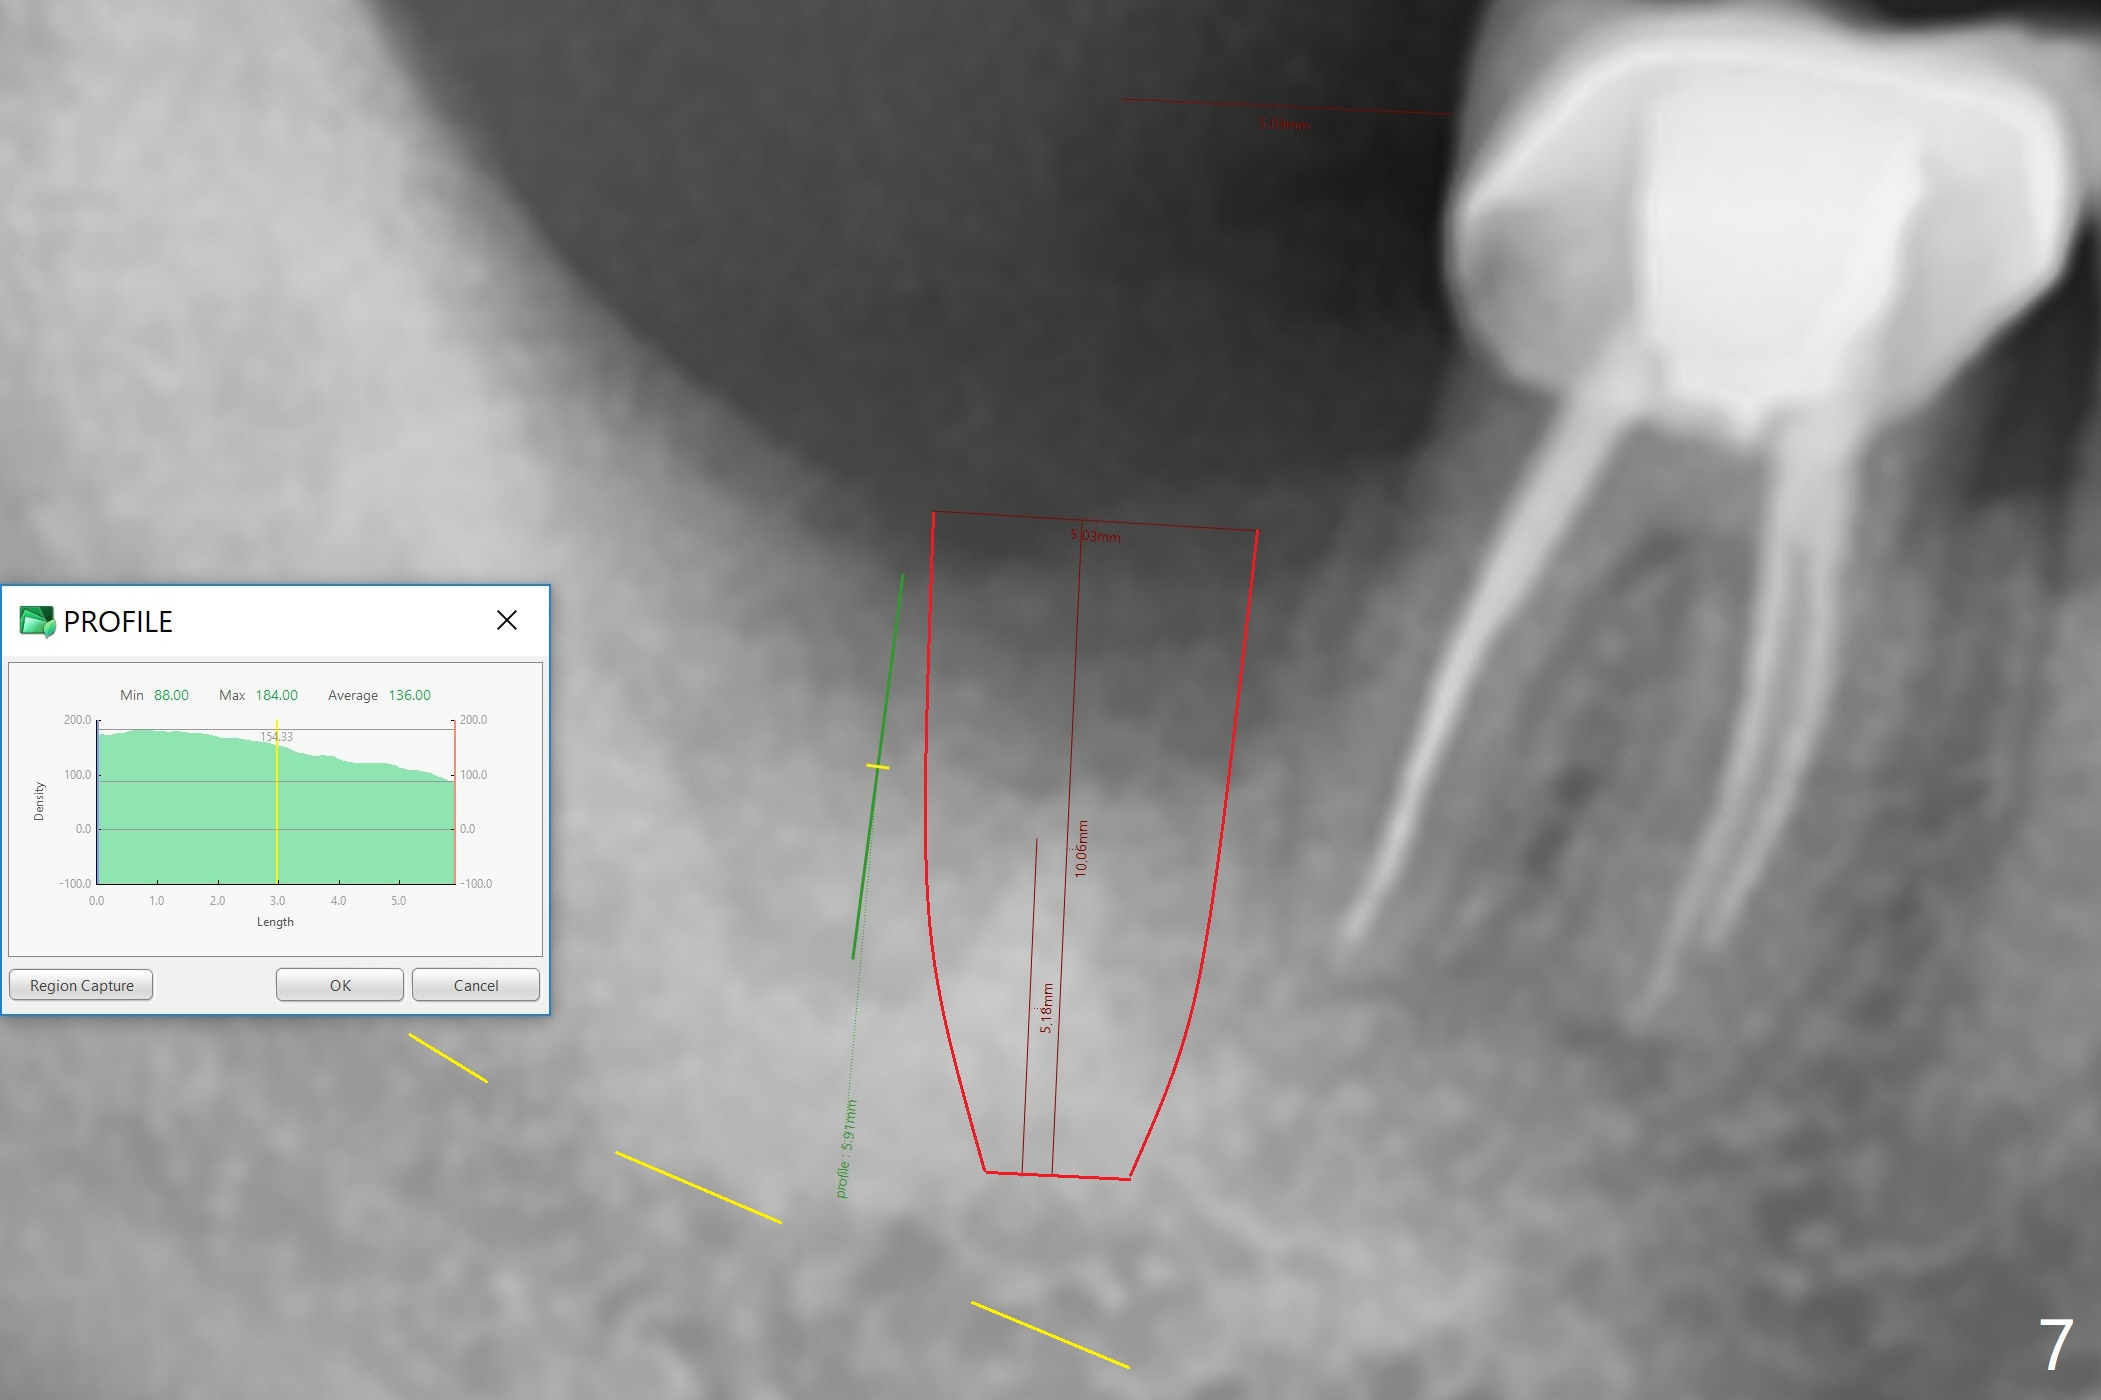

There is a mesiobuccal fistula at #31 with periimplantitis (Fig.1 ^). The bone loss is severe before and after implant removal (Fig.2). It is impossible to place bone-level implant in the original osteotomy due to insufficient bone height. There is pain when a new osteotomy is being initiated in the mesial slope. Following placement of Vera Graft (Fig.3), collagen plug and 6-month resorbable membrane, the wound is closed with suture (mild tension). Postop, there is oozing. Periodontal dressing should have been applied. If the ridge can be preserved in 4-6 months, a 11 mm long implant (Fig.4 green line with 4 mm of the native bone) can be placed with 1.9 mm clearance (red dashed line: the superior border of the Inferior Alveolar Canal); the abutment is estimated to have 4 mm cuff (pink). The socket appears to be healing 8 days postop (Fig.5). The ridge remains wide 5 months post implant removal, although the bone density is low (Fig.6,7 (still ~ 1000 units). It seems that a 5x11.5 mm implant could be placed in the mesiobuccal aspect of the bony defect (Fig.8). For better occlusion, the implant should be shorter (5x8.5 mm) after discussion with the guide lab (Fig.9). Make sure that the most coronal thread is buried by the bone graft, i.e., underneath the crest(>).